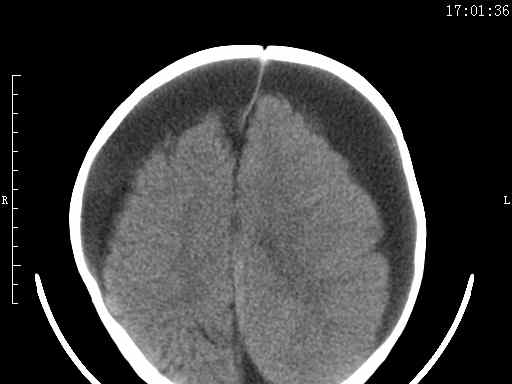

以下是引用余辉在2009-5-30 17:43:00的发言:[br]外围性脑积水在蛛网膜下腔,这个不像,双侧客部液区增宽,内见对称性弧形线状高密度影,边缘清晰锐利,右侧后端终止于冠状缝,左侧终止于人字缝,应该是硬脑膜.双侧硬膜下液区增宽,脑皮质受压变平,脑沟裂无显著增宽,考虑1双侧额颞顶部慢性硬膜外血肿伴硬膜下积液或慢性血肿2双侧慢性硬膜下积液伴硬脑膜剥离并有交通积液(反正考虑硬膜下及硬膜外的慢性血肿或积液)